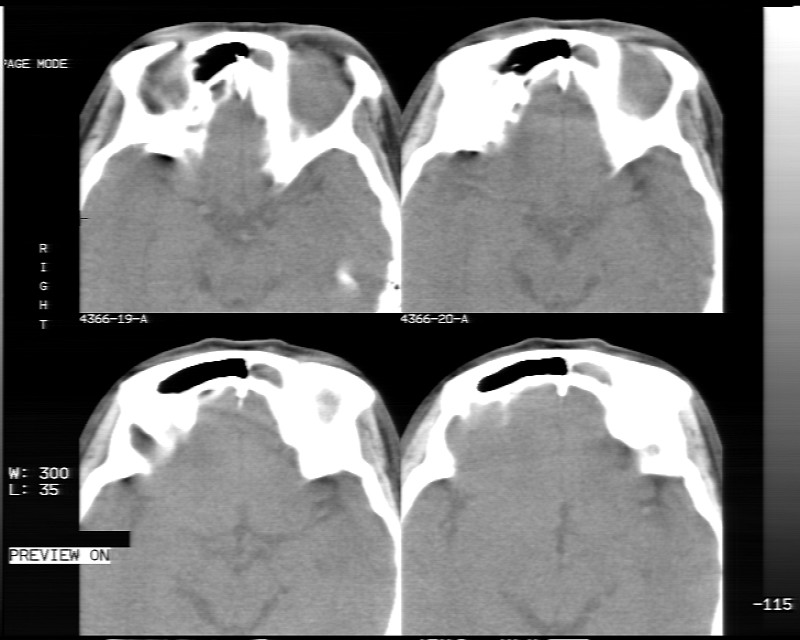

女性,40岁,左眼疼痛,视力模糊,五年曾行左眼脂肪瘤手术。

患者现病史不知持续有多久了,现片示眶内病灶边缘较模糊,眶脂混浊,多考虑炎性假瘤,不除外肿瘤

1)左眼眶内占位性病变,性质待定(不排除炎性假瘤);建议行进一步检查。2)左侧额窦炎。